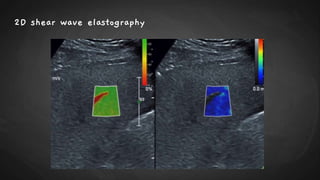

2D shear wave elastography